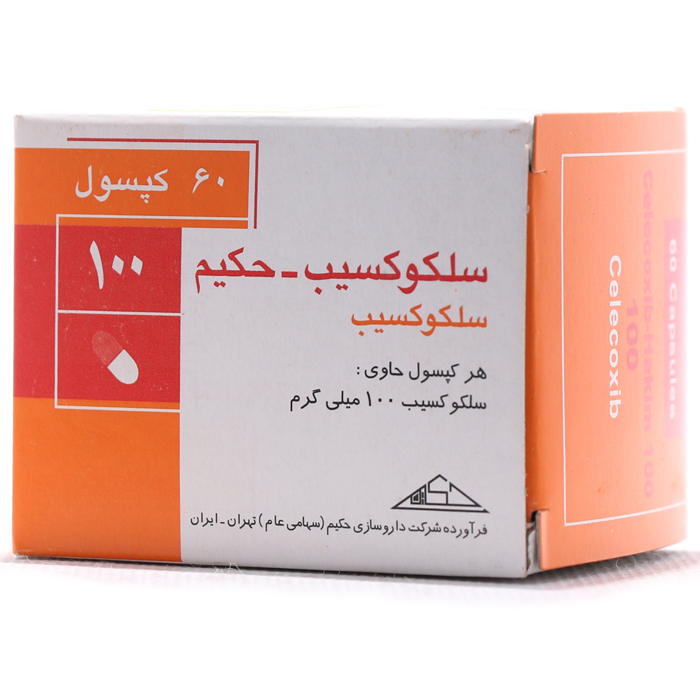

کپسول سلکوکسیب حکیم 60 عددی

نام ژنریک دارو |

سلکوکسیب |

شرکت سازنده/واردکننده |

داروسازی حکیم |

شکل دارو |

کپسول |

دسته مصرفی |

داروهای مسکن-ضد التهاب وضد تب ها |

نام دارو: سلکوکسیب®

ﻧﺎم ژﻧﺮﯾﮏ: سلکوکسیب

ﻃﺒﻘﻪ داروﯾﯽ: داروهای مسکن-ضد التهاب وضد تب ها

ﺷﮑﻞ دارو: کپسول

ﺗﺮﮐﯿﺒﺎت دارو: هر کپسول حاوی: سلکوکسیب 100 میلیگرم